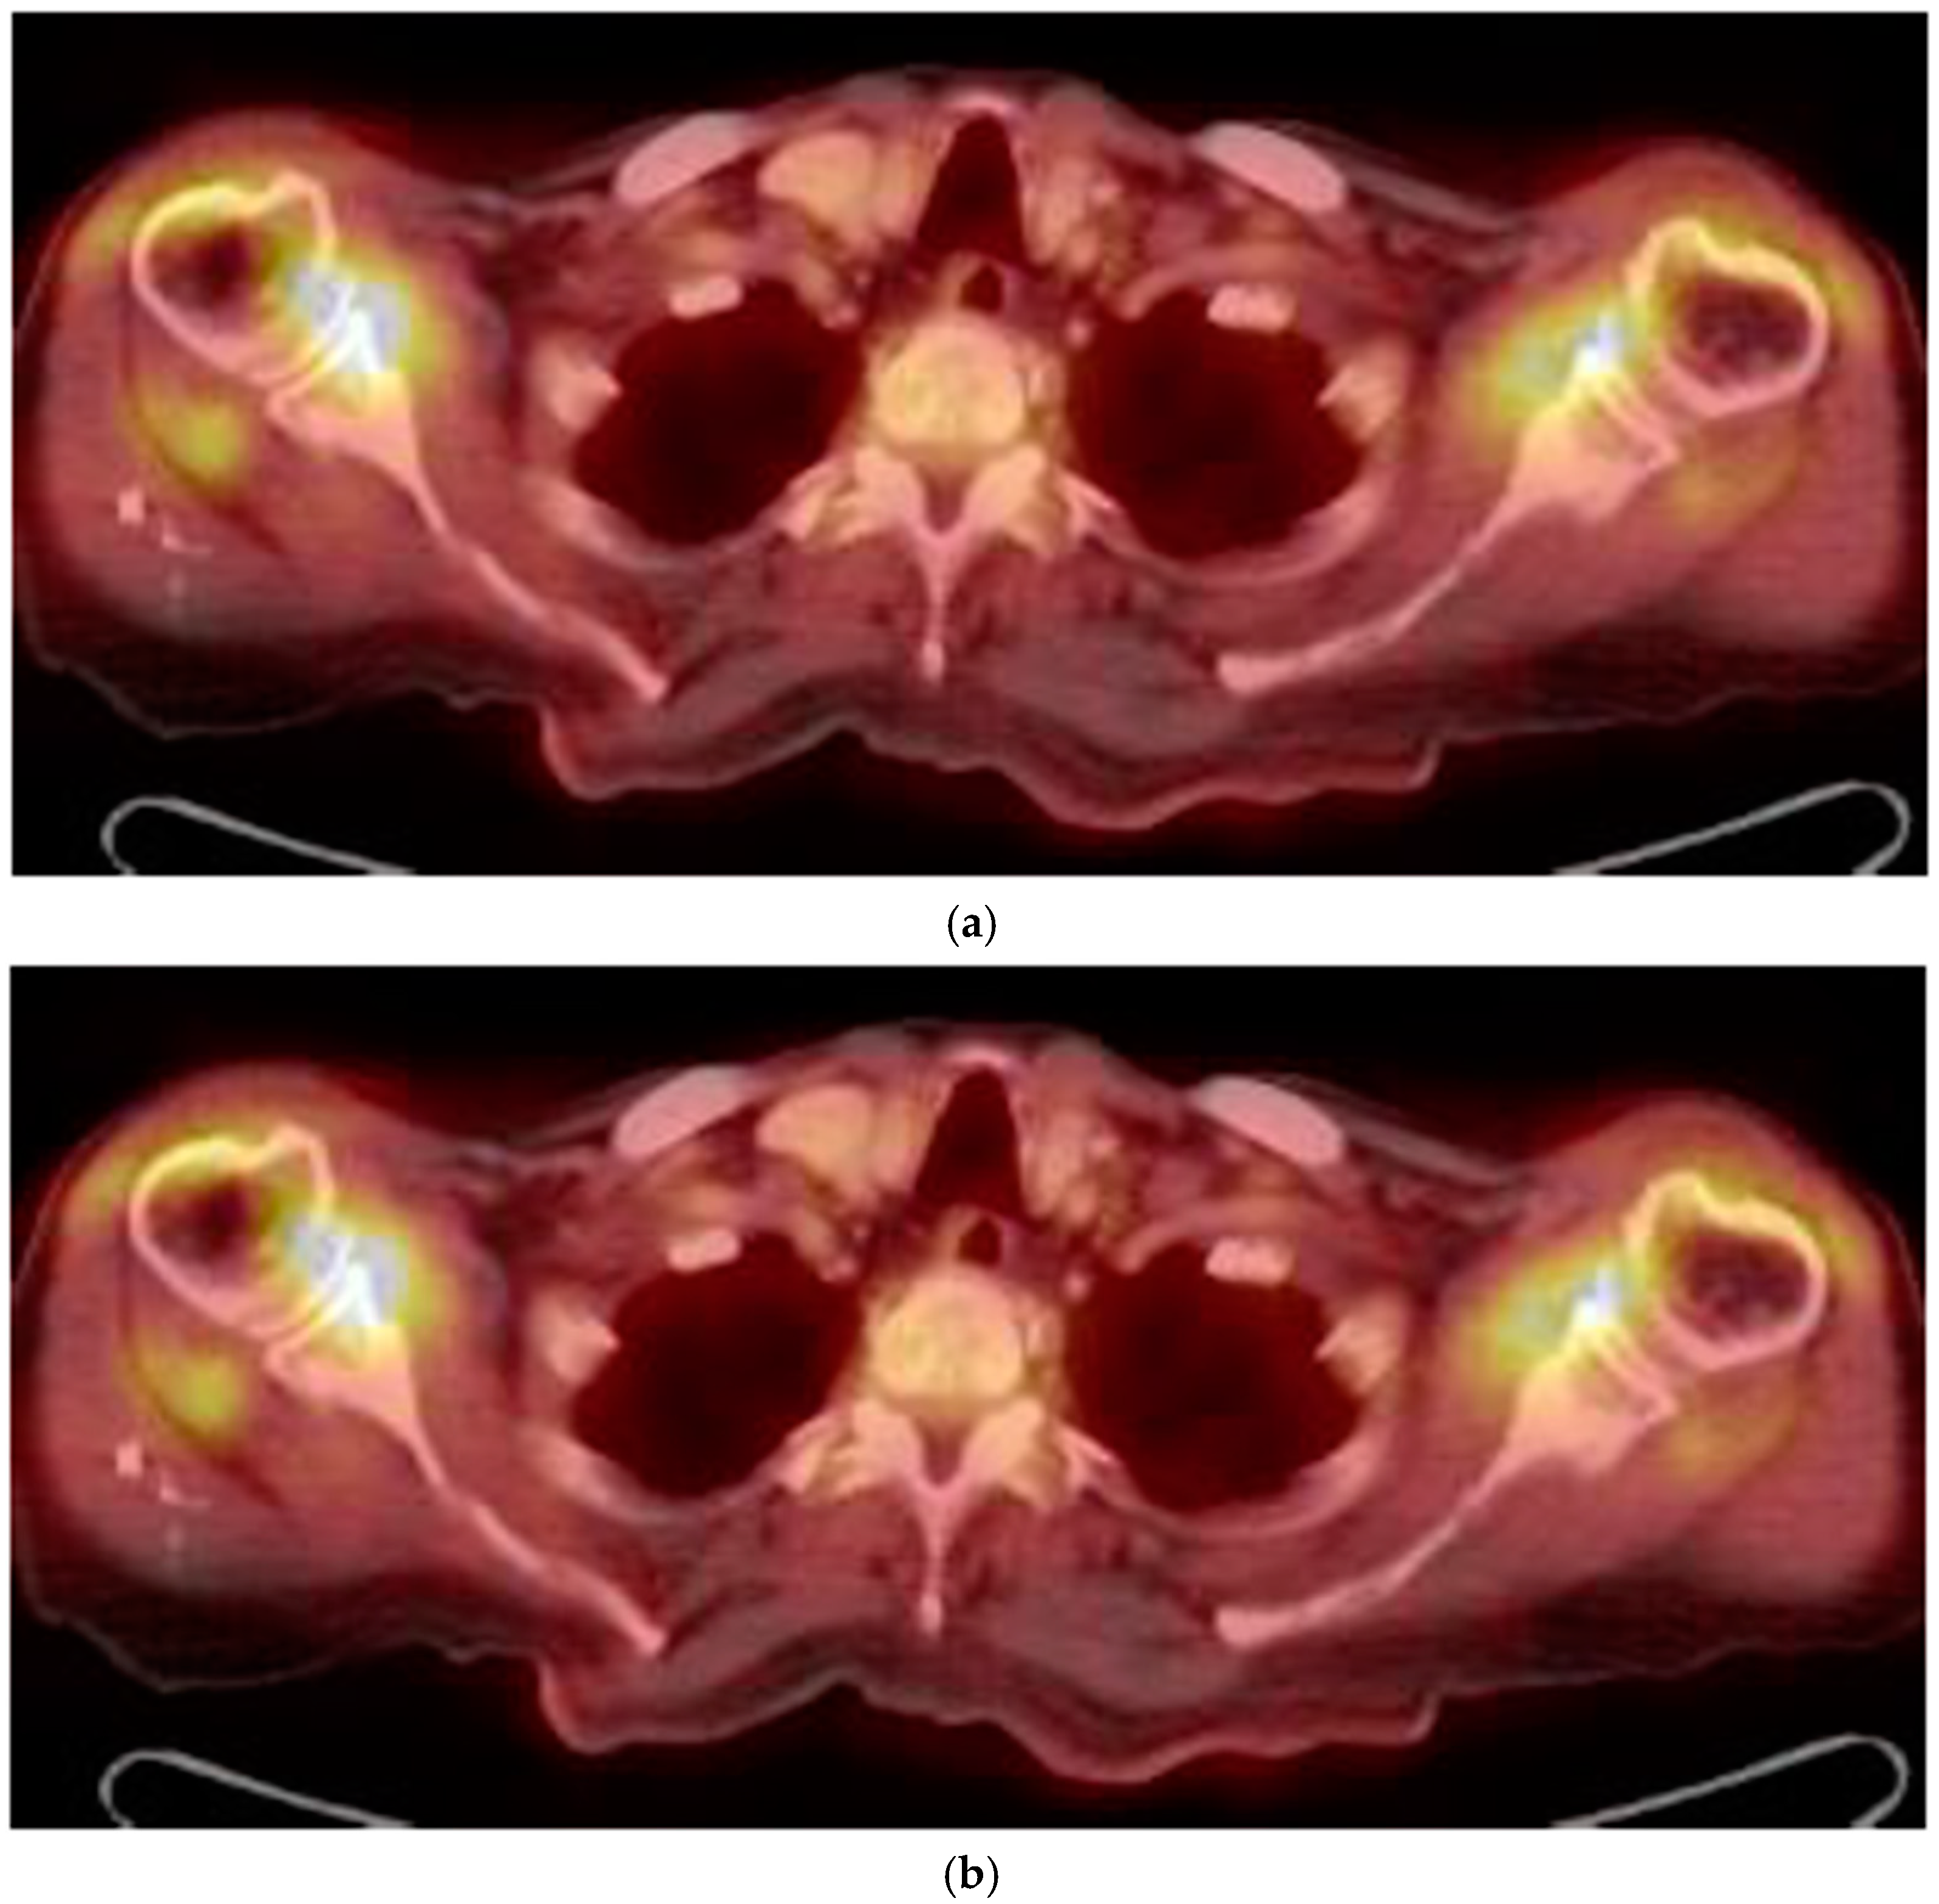

In May 2015, a 100-year-old Caucasian man was referred to our outpatient clinic complaining of chronic pain in shoulder and hip girdle pain with 4-h morning stiffness. Constitutional manifestations were not present. In the previous four months, several non-steroid anti-inflammatory drugs (NSAIDs) and painkillers associated with physiotherapy treatments gave no significant improvement in pain and self-care. He had an X-ray of the chest, shoulders and pelvic, revealing no pathologic findings. An abdominal ultrasound (US) showed mild hepatomegaly and renal cysts. He did not suffer from psoriasis; no ocular, intestinal or uninary manifestations were present. ESR was 21 mm/1st hour (normal values < 30) at the onset and 12 mm/1st hour at the time of our examination. C-reactive protein (CRP) was 4 and 3 mg/dL (normal values < 6), respectively. Other laboratory data were all negative. In particular, serum fibrinogen levels were equal to 350 mg/dL (normal values < 400 mg/dL); rheumatoid factor (RF) and anti-protein citrullinated antibodies (APCA) were in their normal range; hemoglobin was equal to 12.8 gr/dL (normal values > 12.0 gr/dL); transaminases, creatine phospho kinase (CPK), protein electrophoresis, antinuclear cytoplasmic antibodies (ANCA) were in their normal ranges. Occult blood research in the stool was negative and fecal calprotectin dosage was in the normal range. Antibodies to hepatitis C virus and Australia antigen were absent. An US examination showed bilateral long-head-biceps exudative tenosynovitis and subdeltoid bursitis in his shoulders (Figure 1) and trochanteric bursitis in his right hip. An 18-fluorodeoxyglucose positron emission tomography (18-FDG PET) associated with total body computed tomography (CT) was performed (Figure 2) and excluded pathological findings in other sites. PMR was proposed. He started with 12.5 mg/day prednisone and there was a rapid improvement. After 10 days, he spontaneously stopped prednisone, but after 24 h, the manifestations reappeared, and he took it again. Prednisone tapering was made according to the schedule proposed by an international collaborative initiative [10] and stopped after 10 months. The patient refused a control PET/CT. A new US evaluation of shoulders and hips, performed after three months, showed normal findings. During a 3-year follow-up, he never had constitutional manifestations; no clinical manifestations suggestive for an overlapping giant cell arteritis (GCA) were observed; no alternative diagnosis was possible. As for today, our patient is fine.

Figure 2.

(a) FDG uptake in both the shoulder (18-FDG PET/CT fused axial slice); (b) FDG uptake in hips and subtrochanteric bursae.

Up to now, in absence of a specific diagnostic test, the diagnosis of PMR remains clinical. In the last years, classification criteria proposed by a European League Against Rheumatism/American College of Rheumatology (EULAR/ACR) collaborative initiative highlighted US examination of both shoulders (showing glen-humeral synovitis, bursitis or biceps tenosynovitis) and hips (showing joint synovitis or trochanteric bursitis) [14]. 18-FDG PET/CT findings, even if not pathognomonic, are equally important for improving diagnostic accuracy [15,16]. In our patient, US examination and 18-FDG PET/TAC showed symmetrical inflammatory findings, exclusively located in his shoulder and hip girdles. CT findings of sacroiliac joints were reported as normal. Moreover, his pain and selfcare had a fast improvement after prednisone introduction with rapid relapse when he decided to suspend it. When we piece the puzzle together, the diagnosis of PMR was the only possible one. After a 3-year follow-up, no alternative diagnosis was found. What else could he have suffered from?